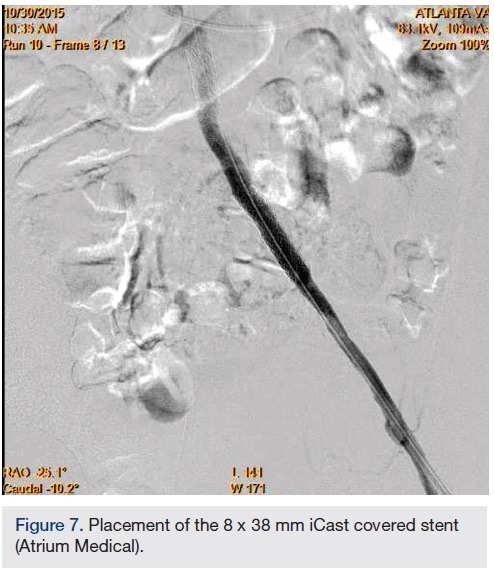

In view of the increased complexity of this situation and potentially prolonged procedure times with increased risk of complications, we chose to stage the procedure in two phases: peripheral and coronary. Accordingly, the patient was brought in, the left common femoral artery was accessed using a micropuncture technique, and a 10 cm, 7 French sheath was placed in the artery. Angiography of the left iliofemoral system was performed using a 4 French multipurpose catheter. This was followed by IVUS, revealing a 38.1 mm2 reference segment area and a minimum 8.6 mm2 stenosis area, equating to an 80% area stenosis within the left external iliac artery (Figures 5-6). The wire was exchanged for a 260 cm Rosen wire (Cook Medical) and the lesion was first predilated with a Workhorse II 6 mm balloon (AngioDynamics) at 10 atmospheres for 60 seconds for two successive inflations. The balloon was then removed over the wire and the short 7 French sheath was exchanged over the wire for a 25 cm, 7 French sheath, which was advanced over the Rosen wire into the distal aorta. An 8 mm x 38 mm x 120 mm iCast covered stent (Atrium Medical) was then advanced to the level of the stenosis and unsheathed via retraction of the 7 French long sheath. The stent was deployed at 10 atmospheres for 60 seconds. There was still a small waist in the proximal stent and this was post dilated with the stent balloon at 13 atmospheres for 90 seconds with excellent angiographic result and no evident perforation or dissection, yielding 0% residual stenosis (Figure 7).